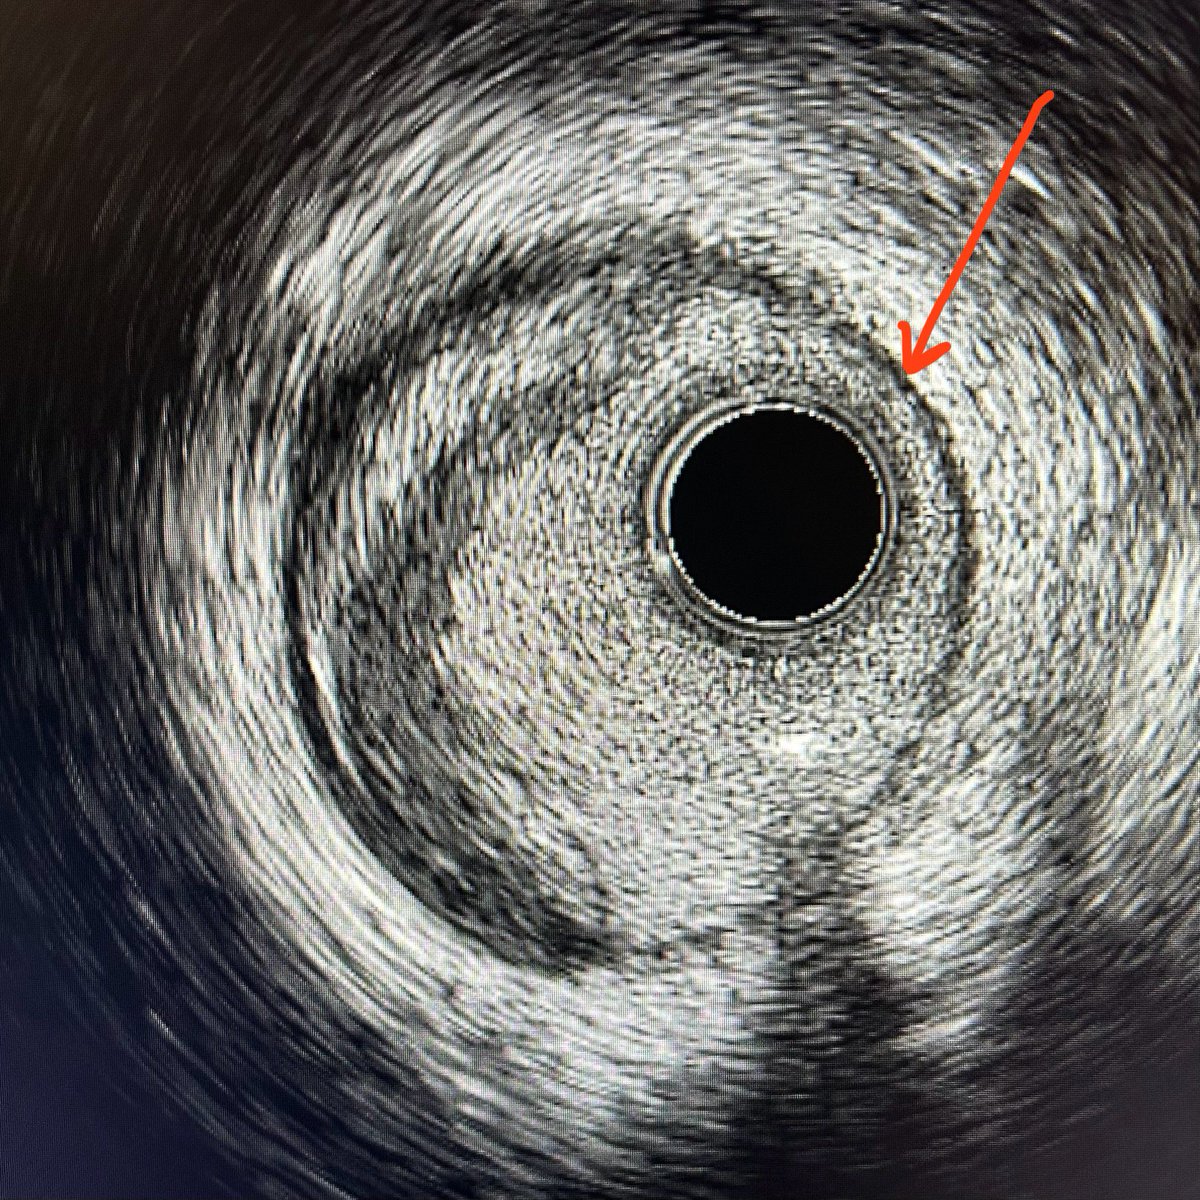

Doing solo-operator ROTAPRO

(rotational atherectomy)